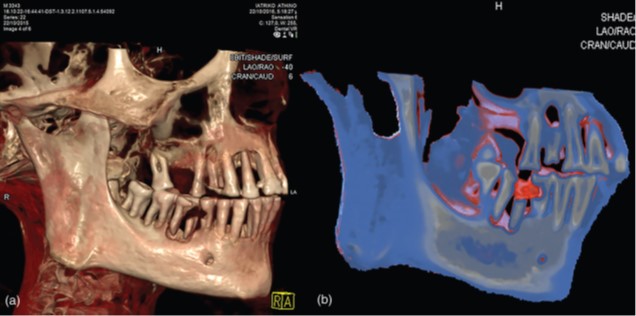

Esistono almeno un paio di testimonianze di protesi (forse) effettuate in vita e (forse) non per motivi estetici sul defunto. Un secondo e terzo molare uniti da un filo d’oro risalenti al 2500 BCE sono stati ritrovati a Giza e costituivano forse il tentativo di bloccare il terzo molare, che aveva perso le radici per un’infiammazione, al secondo molare (“Ponte di Giza”).

Un impianto simile, che legava un canino agli incisivi, di cui almeno uno mancante, è stato ritrovato invece ad el-Quatta tra i resti di un cranio distrutto. Un terzo impianto, sicuramente effettuato in vita e risalente all’epoca tolemaica, potrebbe essere stato effettuato in Egitto ma ci sono molti dubbi al riguardo. In tutti i casi, gli studiosi discutono (animatamente) se siano effettivamente protesi o amuleti.

Altri due ponti dentali, risalenti al V-IV secolo BCE, sono stati ritrovati intorno a Sidone ma in tombe contenenti oggetti egizi, per cui esiste la possibilità che fossero stati creati in Egitto o comunque da dentisti egizi.